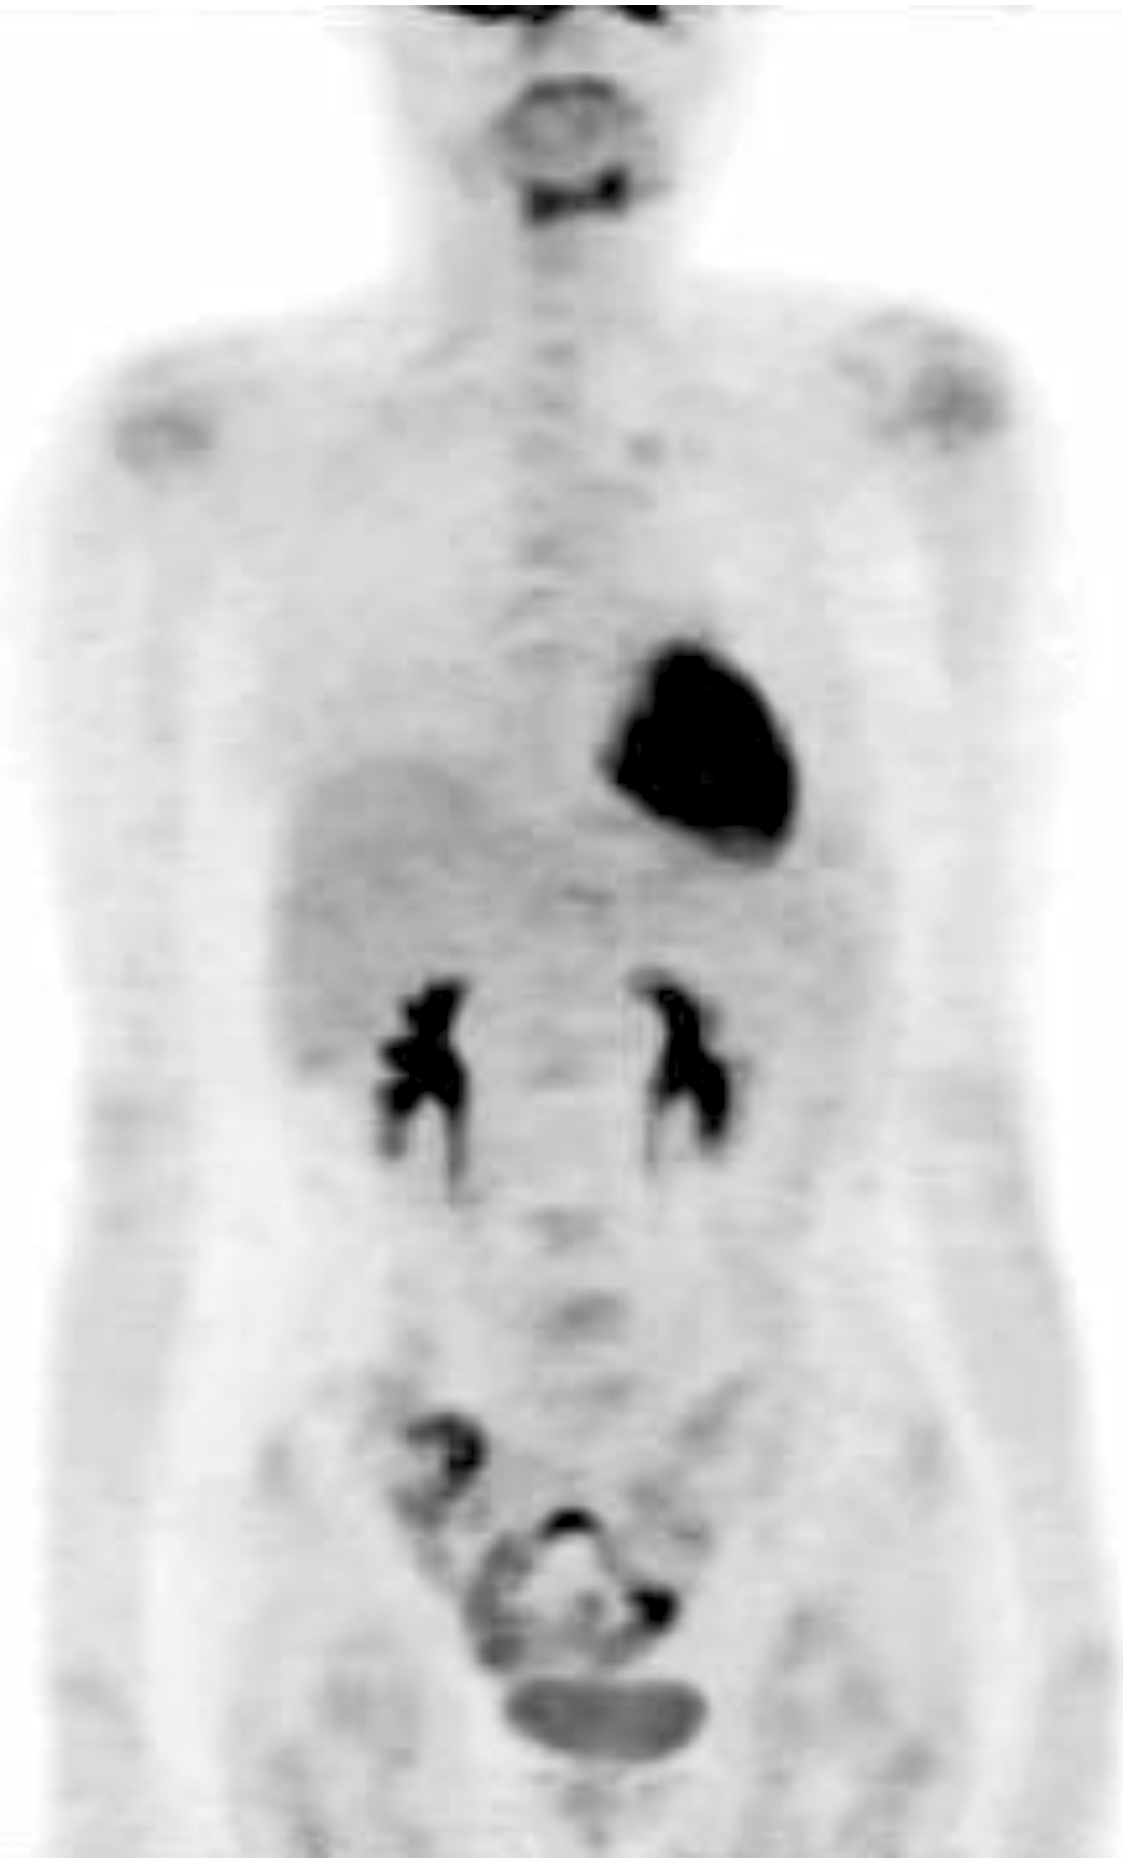

张国淳:该患者在术后再予2周期XT方案化疗后予内分泌维持治疗, 方案为戈舍瑞林卵巢去势加阿那曲唑, 并予氯膦酸二钠抗骨转移治疗。患者在2010年4月行PET复查时发现左上肺、肝左叶及全身多处骨髓局灶性葡萄糖代谢异常增高灶, 与前次PET影像比较, 以上均为新发病灶(见图5)。患者一线治疗的无进展生存期为8个月。患者此时拒绝化疗。改用依西美坦内分泌治疗。2010年8月复查胸腹部CT提示双肺多发性转移癌, 右侧胸腔积液, 纵隔、肺门淋巴结肿大, 肝多发性转移瘤, 多发性骨转移瘤, 提示疾病再次进展, 见图6和图7。患者此时同意任何形式的治疗, 包括化疗。那么此时应该如何选择治疗方案?